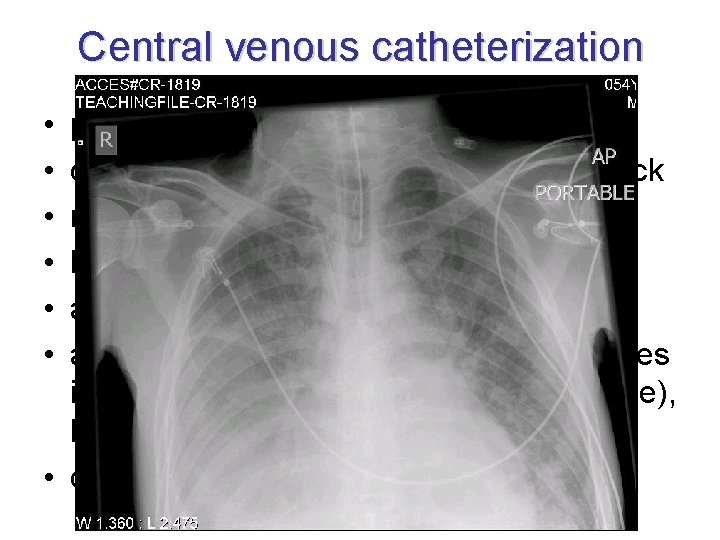

Central venous catheterization • v. jugularis int. • v. subclavia – infraclavicular (less supraclavicular approach) • v. femoralis (urgent approach) • v. axillaris, v. mediana cubiti, v. jugularis ext. • v. umbilicalis (newborns) • complications: infection, pneumothorax, hemothorax, plexus brachialis injury, air embolism

Central venous catheterization • • • permanent venous approach central veins do not collapse during shock monitoring of central venous pressure large volume replacement application of parenteral nutrition application of catecholamines, substances irritating venous wall (cytostatics, glucose), high-osmolar solutions • dialysis

Wrong position of catheter